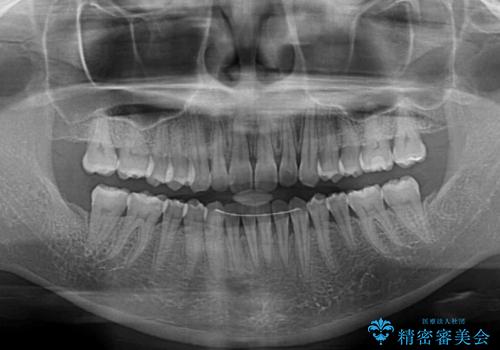

- 前歯のデコボコで前方に出ていることを気にして来院された患者様です。

上顎前歯が捻れて前方に飛び出しており、下顎前歯もそれに沿うようにデコボコとなっていました。

IPR(歯と歯の間を削る処置)によりスペースを獲得して上下顎前歯のデコボコを改善し、飛び出している前歯が引っ込むように設定し、インビザラインにて矯正治療を行うこととしました。

装着時間を守ってくださったので、予定通りの期間で終えることができました。インビザライン特有の、奥歯の咬み合わせの問題もなく、しっかりと歯列を改善することができました。